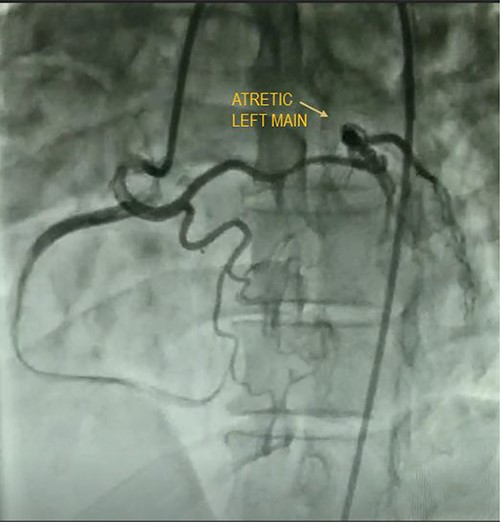

Case 3

A quadragenarian gentleman presented to cardiology out patient department (OPD) with complaint of a central chest discomfort with normal electrocardiogram (ECG) and echocardiography. His treadmill test came positive for inducible/reversible ischemia with modified Bruce Protocol. His CAG shown in Fig. 4 reveals an atretic left main coronary artery with circulation from RCA. He was referred to us for coronary artery bypass graft (CABG) and underwent LIMA–LAD, radial artery to diagonal and obtuse marginal artery bypass with a smooth postoperative recovery.